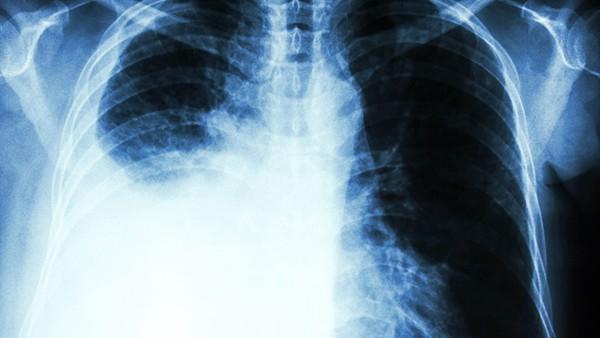

肺动脉高压是一种常见且严重的疾病,其发病过程受到多种因素的影响,其中遗传因素在其发病机制中扮演着重要的角色。遗传因素对于肺动脉高压的发病可能涉及多个遗传变异和基因突变,这些遗传变异可能导致血管功能发生异常,从而引发肺动脉高压的发展。 研究表明,一些家族性疾病中存在明显的肺动脉高压发病倾向,这提示了遗传因素在疾病发生中所起的作用。例如,家族性肺动脉高压是一种罕见但严重的遗传性疾病,在家族中有患者遗传给下一代的概率较高。此外,一些研究发现,特定基因的突变可能会增加患肺动脉高压的风险,这进一步证实了遗传因素和肺动脉高压之间的关联。 遗传因素不仅影响肺动脉高压的发病风险,还可能影响疾病的发展和预后。一些研究表明,特定基因突变可能导致肺动脉高压的严重程度增加,甚至影响患者对治疗的反应。因此,了解遗传因素在肺动脉高压中的作用对于疾病的早期诊断、治疗和预后判断至关重要。 在未来,随着遗传学和基因组学技术的不断发展,我们对遗传因素和肺动脉高压之间关系的理解将会不断深化。这将有助于我们更好地预测肺动脉高压的发病风险,开发个体化的治疗方案,改善患者的生存质量,为肺动脉高压患者带来更好的医疗保健。 综上所述,遗传因素与肺动脉高压之间存在着密切的关联。通过深入研究遗传因素在肺动脉高压发病机制中的作用,我们可以更好地理解这一疾病,并为患者提供更有效的治疗手段和干预措施,助力肺动脉高压患者的健康。